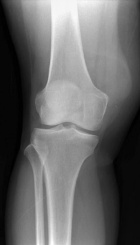

V.D. - 51 year old woman with intermittent right knee pain and swelling after twisting it three years ago

Zoom image: Radiological image Radiological image.

Zoom image: Cell stain Cell stain.